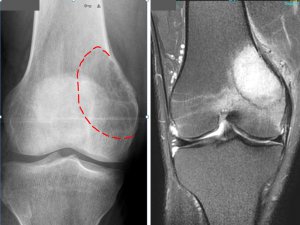

Kemik tümörü olarak adlandırılan Herediter Multipl Ekzositoz (HME) tanısı konulan Birhat, hastanenin ortopedi kliniği doktorları Op. Dr. Recep Dinçer ve ortopedi el cerrahisi uzmanı Op. Dr. Avşin Öztürk tarafından tedavi edildi.

Dinçer, yaptığı açıklamada, Birhat'a koydukları HME hastalığının 50 binde bir görülen rahatsızlık olduğunu belirterek, şunları kaydetti:

"Vücutta yaygın şekilde tüm ekstremitelerde (kol, bacak) kitle ve çıkıntıların oluşmasıyla fark edilir. Vücuttaki bu yaygın kitleler genel olarak iyi huylu tümörlerden oluşmaktadır. Fakat yüzde 10 kötü huylu tümöre dönüşme ihtimali de vardır. Büyük yumru şeklindeki kitleler ağrıya ve hareket kısıtlılığına yol açarak yüzde 90 oranında günlük yaşam aktivitelerini engeller. Sıklıkla hayatın ilk on yılında görülür."

Yaklaşık 2 yıldır, 6 aylık periyotlar halinde gözetim altında tuttukları Birhat'ın son dönemde rahatsızlığının iyice fark edilir ve hareketi kısıtlar ve uzuvlarda kısalığa yol açar hale geldiğini anlatan Dinçer, uygulanan tedaviyle ilgili şu bilgileri verdi:

"Damar ve sinir hasarı göz önünde bulundurularak el cerrahisi uzmanımız Op. Dr. Avşin Öztürk ve Op. Dr. Tuncay Baran ile Birhat’ın ameliyatını gerçekleştirdik. Erzurum’da ve bu bölgede bir ilki başardık. Ön kol kemikleri dediğimiz kemiklerdeki eğriliği giderdik ve kısa olan diğer ön kol kemiği keserek dışarıdan yerleştirdiğimiz fiksatörler ile uzatma uygulayacağız. Sağ bacaktaki şekil bozukluğuna yol açan tümörleri de çıkarttık. Ameliyat gayet güzel ve başarılı şekilde tamamlandı. Bundan sonraki 3 aylık süreçte kol kemiklerini uzatacağız ve şekil bozukluğunu gidereceğiz."